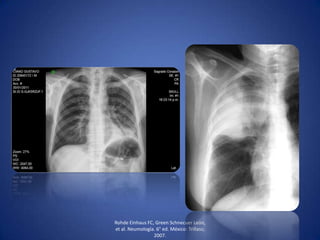

• Cuando además de líquido, existe aire en la cavidad

pleural (fístula broncopleural o introducción accidental

de aire a la cavidad pleural durante una punción).

• Líquido se acumula en las partes declives y el aire en la

parte superior.

Hallazgos radiológicos de

hidroneumotórax

• Opacidad homogénea que

borra senos

costodiafragmáticos,

cardiofrénicos y diafragma.

• Nivel hidroaéreo.

• Desplazamiento de la sombra

mediotorácica hacia el lado

contrario.